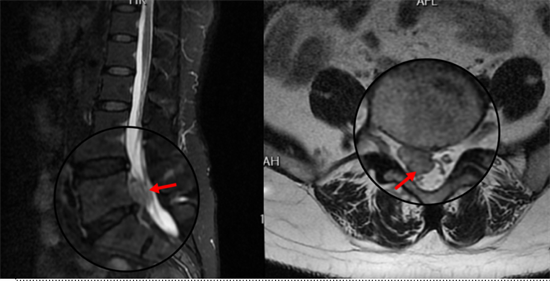

術(shù)后復(fù)查MRI顯示脫出椎間盤(pán)完全摘除,

神經(jīng)松解徹底,患者術(shù)后恢復(fù)良好